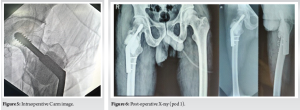

The patient was placed in a supine position on a fracture table. Fracture reduction was achieved through manual traction and digital manipulation, with confirmation under fluoroscopy. A curvilinear skin incision, approximately 10 cm in length, was made distal to the greater trochanter. Superficial dissection was performed, the iliotibial band was incised along the incision line, and the vastus lateralis was split and retracted anteriorly. The proximal femur was exposed, and the lateral cortex over the proximal femur was opened. Intralesional curettage of the tumor was done utilizing fluoroscopy. The cavity was packed with hydrogen peroxide soaked gauge. An intraoperative biopsy sample was collected for histopathological examination. A DHS angle guide (135°) was used, and a guidewire was inserted through it up to the subchondral location in the femoral head, confirmed under fluoroscopy in both anteroposterior and lateral views. Triple reaming was performed along the same path. An 80 mm Richard screw was inserted, followed by the introduction of the DHS plate with cortical screws. Bone cement was then injected into the scooped area of the proximal femur (Fig. 4). The remaining screws were inserted, and the fracture reduction, along with the position of the plate and screws, was confirmed under fluoroscopy (Fig. 5).

Postoperatively, X-rays were taken (Fig. 6), and no complications were seen. The patient was advised non-weight-bearing mobilization for 6 weeks, and then weight-bearing was started gradually.